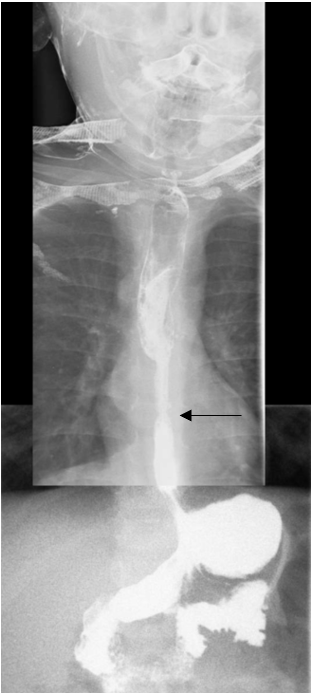

Subsequently, the boy successfully underwent a double-contrast upper GI study (Figures 1 and 2). An esophageal stricture was identified involving the lower one-third of the esophagus. The esophagus was foreshortened, with a moderate-sized hiatal hernia secondary to traction. Proximal esophageal dilatation was present. No gastroesophageal reflux (GER) was noted during examination; however, the findings were in keeping with chronic/recurrent longstanding GER with secondary esophageal stricture.

Figure 2. Upper GI series with barium contrast, anteroposterior view. The irregular stricture is again visible in the distal esophagus. Proximal dilation and a mildly foreshortened esophagus is evident. A hiatal hernia secondary to traction is visible. The intrathoracic gastroesophageal junction is indicated by the black arrow.